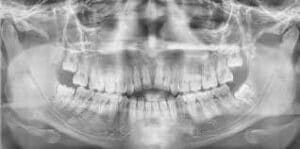

Más de 4 mil cadáveres de crematorios y laboratorios médicos han sido sometidos a investigación por su posible relación con la sustracción de huesos para la elaboración de injertos dentales.

Esta investigación surge en Taiyuan, una ciudad en China donde la policía ya investiga el robo de más de 4 mil cadáveres para la producción de injertos óseas alogénicos, que se realizan en cirugías previo consentimiento de los donantes.

Los injertos óseos alogénicos en odontología, se utilizan principalmente para regenerar el hueso perdido, preparando el maxilar o la mandíbula para procedimientos como implantes dentales.

Así, hay distintos tipos de injertos y los injertos óseas alogénicos se refieren a un hueso humano procesado en el laboratorio; el hueso proviene de un donante fallecido de un banco de tejidos óseos.